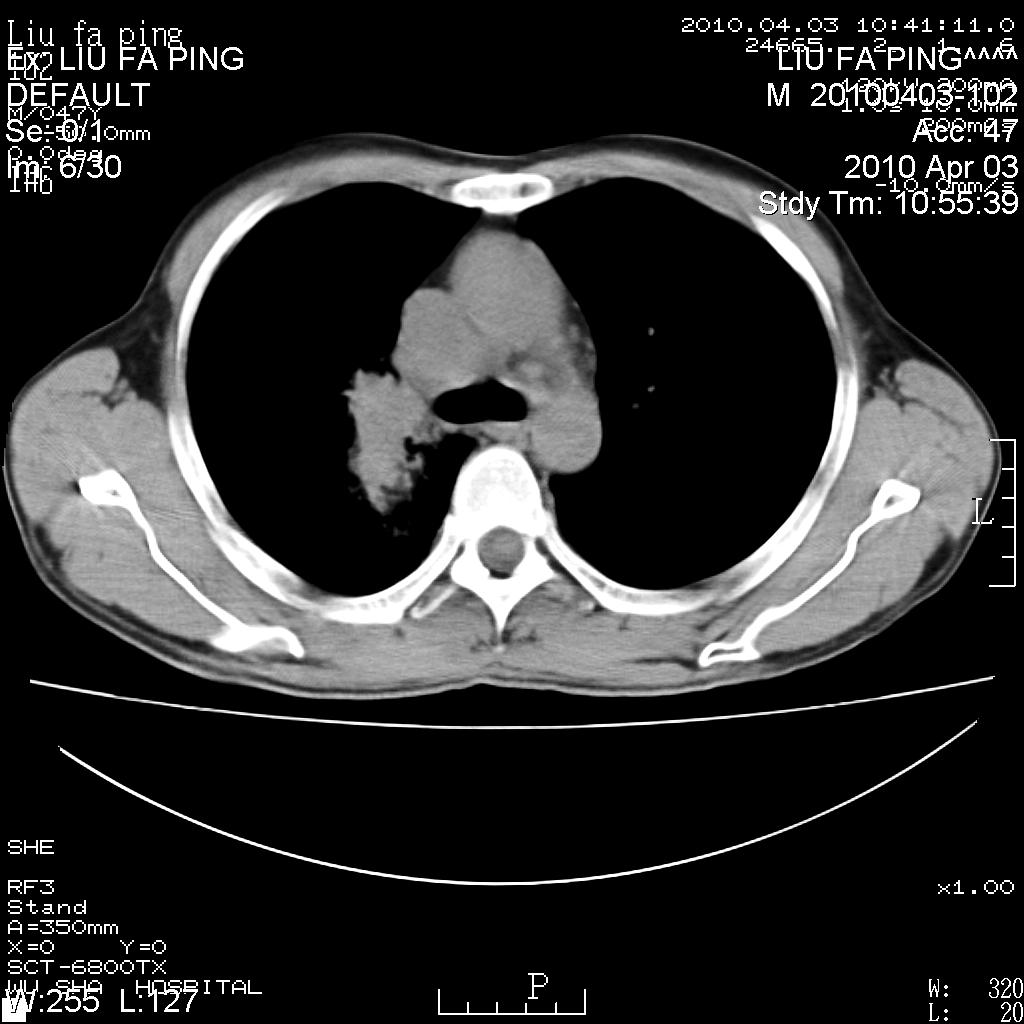

标题: CT25875:咳嗽数天。

平时身体健康,无不适

男性47岁,考虑中心性肺癌合并阻塞性肺炎,纵膈淋巴结肿大。肺内及纵膈淋巴结钙化。

建议支气管镜检

支持右侧中央型肺癌伴右肺上叶阻塞性炎症、纵膈淋巴结转移,建议纤支镜检查!

男性47岁,考虑中心性肺癌合并阻塞性肺炎,纵隔淋巴结肿大。肺内及纵隔淋巴结钙化。

考虑右肺中央型肺癌并阻塞性肺炎,右肺门及纵隔淋巴结转移;建议必要时行纤支镜检查进一步明确诊断。